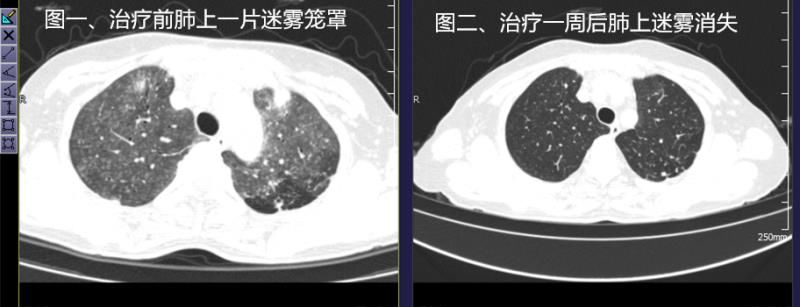

相关检查显示,徐女士的结核病并没有复发,不过她CT片显示,肺部形成一层灰蒙蒙的迷雾。这预示着,有炎症渗出。那么是什么导致了炎症的发生呢?

杨澄清说,蘑菇种植场的阴湿环境有益于蘑菇真菌的生长。但由于个体差异的原因,有人对真菌、细菌、原虫、动物蛋白(鸟类常见)以及低分子量化合物过敏。·这些过敏源吸入肺部后,对上述物质过敏者就会出现肺泡炎症渗出的情况,表现在CT上就是灰蒙蒙一片迷雾,也叫作磨玻璃影。因为过敏源隐藏于生活、工作各处,常不引人瞩目,所以,不容易被人注意,医生如果询问有遗漏,就可能造成误诊。